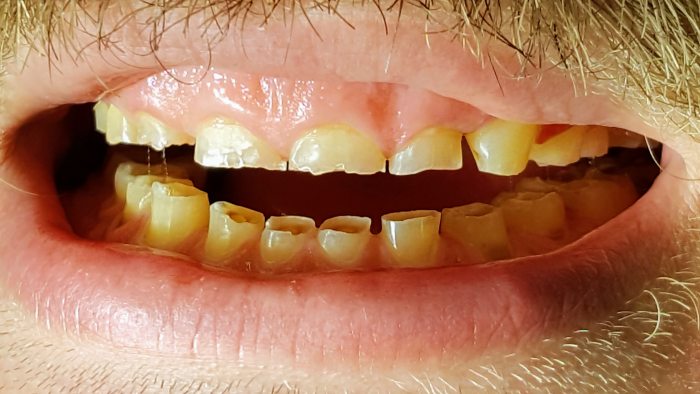

HOIDOT PURENTAVAIVOIHIN

On paljon hammasvaivoja, joihin on olemassa helppojakin hoitoja. Asiantuntevalta hammaslääkäriltä saat hammastarkastuksessa analyysin oman suusi terveydestä. Tässä kuvassa potilaan vaivana oli purressa lohkeavat hampaat. Kyseessä oli kuluneiden hampaiden väärään asentoon ohjaama (eli ristipurentaan) purenta ja sen myötä syntyneet lisävauriot, kulumat ja lohkeamat. Nämäkin hampaat hoidettiin kuntoon, suun terveys palautui ja ilmeestä tuli entistä ehompi, raikas ja hurmaava. Lue koko purentahoidon eteneminen tästä ja katso hämmästyttävät kuvat ennen ja jälkeen.

purentavirhe, ristipurenta